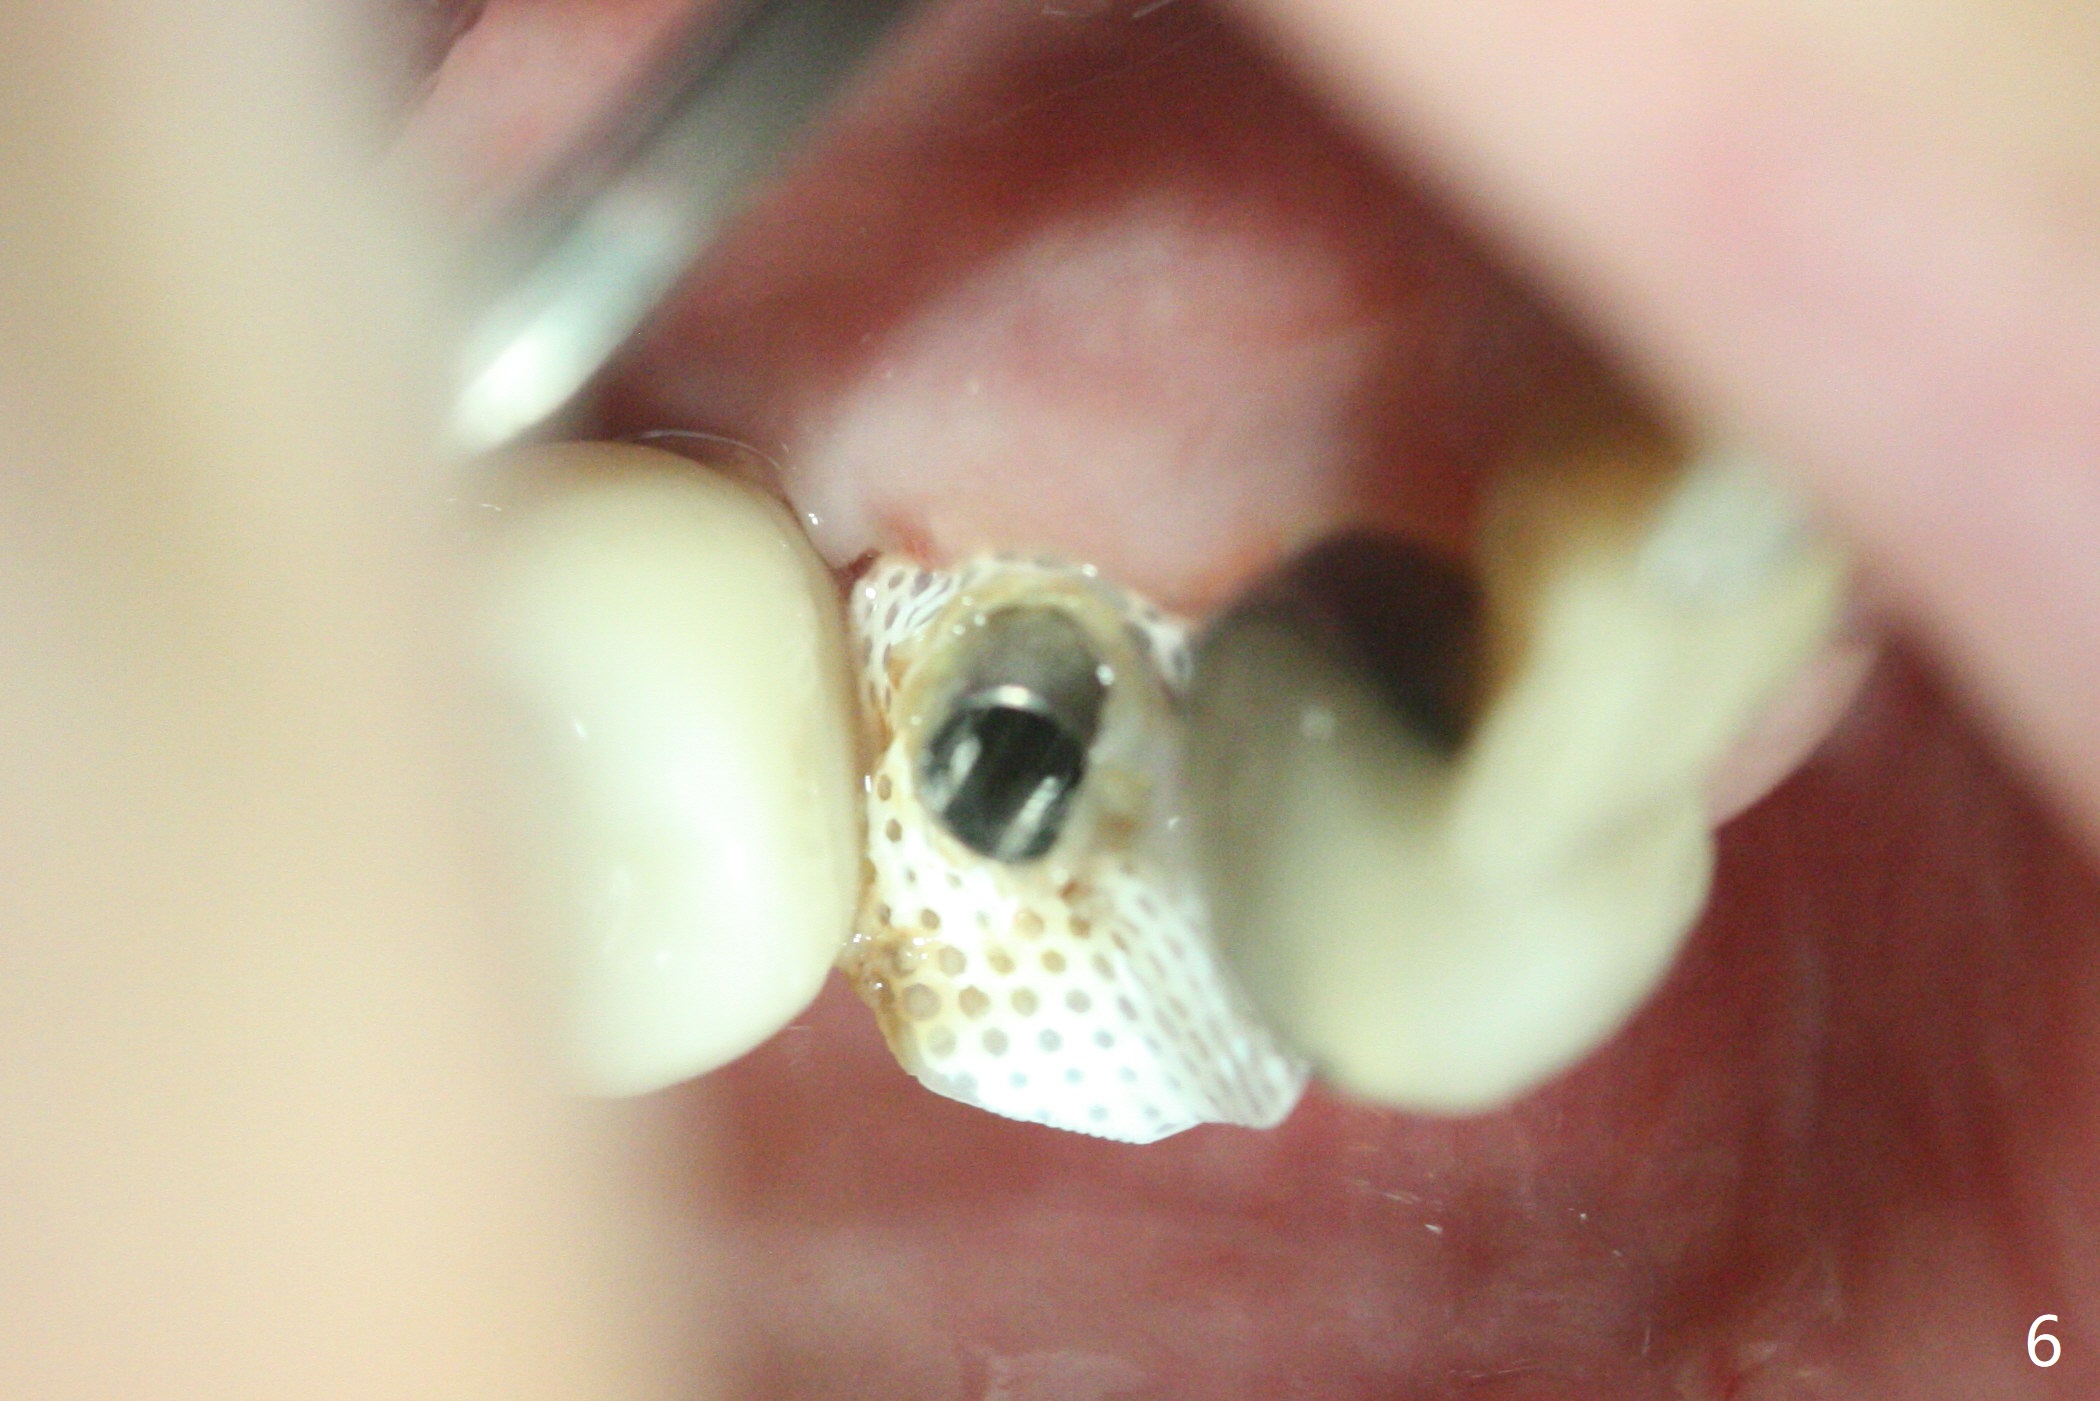

28牙位3.5x8.5毫米植体导板植入后,颊侧远中螺纹暴露,为了植骨,附近骨壁钻洞创造出血点以及放置基台(图一:5x7.5(3)毫米)。放置粘性骨粉后(图二:*),覆盖薄层PRF,后者可能很快吸收,为了防止骨粉暴露,放置不可吸收膜(图三:*),当中打洞,穿过基台固定,表面缝合。术后六周不可吸收膜部分暴露(图四)。图五,六显示在取出时膜当中固定用的洞,下面伤口愈合正常(图七)。